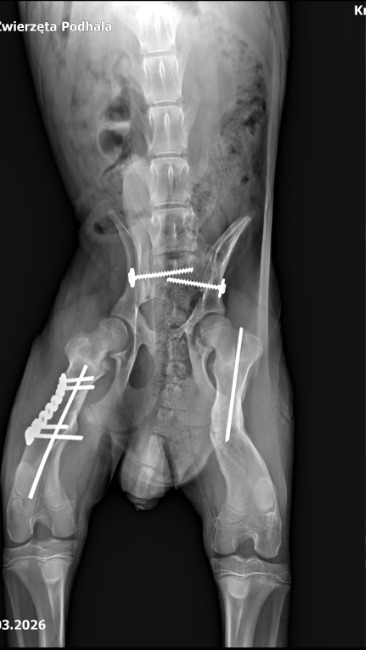

Klimek miał kilka miesięcy kiedy został potrącony przez samochód. Słaby układ kostny szczenięcia nie wytrzymał tak silnego uderzenia, złamaniu uległy obie tylne łapy oraz miednica.

Zespół weterynarzy spędził przy stole operacyjnym wiele godzin, zanim udało im się poskładać Klimka w jedną całość.

Podczas drugiej operacji, która odbyła się 24.02.2026 Klimek "pozbył" się jednej śruby, która mocowała miednicę oraz gwoździa z lewej łapy.

21.04.2026 po raz kolejny musimy zawieźć psiaka do lecznicy, i po raz kolejny położyć go na stole operacyjnym. Tym razem trzeba usunąć drugą śrubę z miednicy, zabieg ten ma na celu poprawienie ruchomości układu kostnego, który rośnie razem z psem, a jest ograniczona właśnie tym implantem.